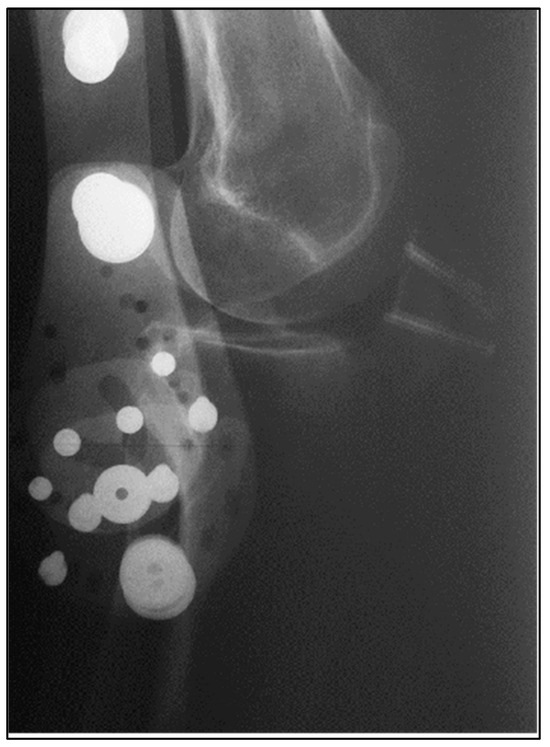

| Graft Signal Intensity | Mildly increased on T2 | Mildly increased on T2 |

| Fiber Continuity | Continuous alignment, minor edema | Continuous alignment, minor edema |

| Bone Block Integration | Early bridging at the patella | Early bridging at the calcaneus |

| Hardware Artifact | Minimal, no screw loosening | Minimal, no screw loosening |

| Signs of Complication | None | None |

| Bone Block Union (X-ray) | Complete union, no hardware issues | Complete union, no hardware issues |